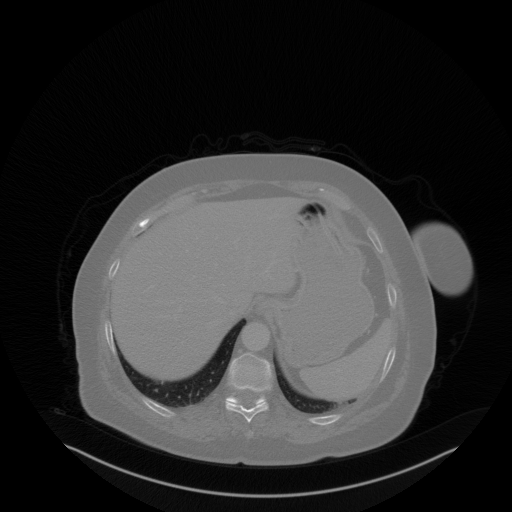

Original VENOUS CT scan

No window - Raw intensity values

Lung window (WL -600, WW 1500 β†’ Low βˆ’1350, High +150)

Mediastinum window (WL 40, WW 400 β†’ Low βˆ’160, High +240)